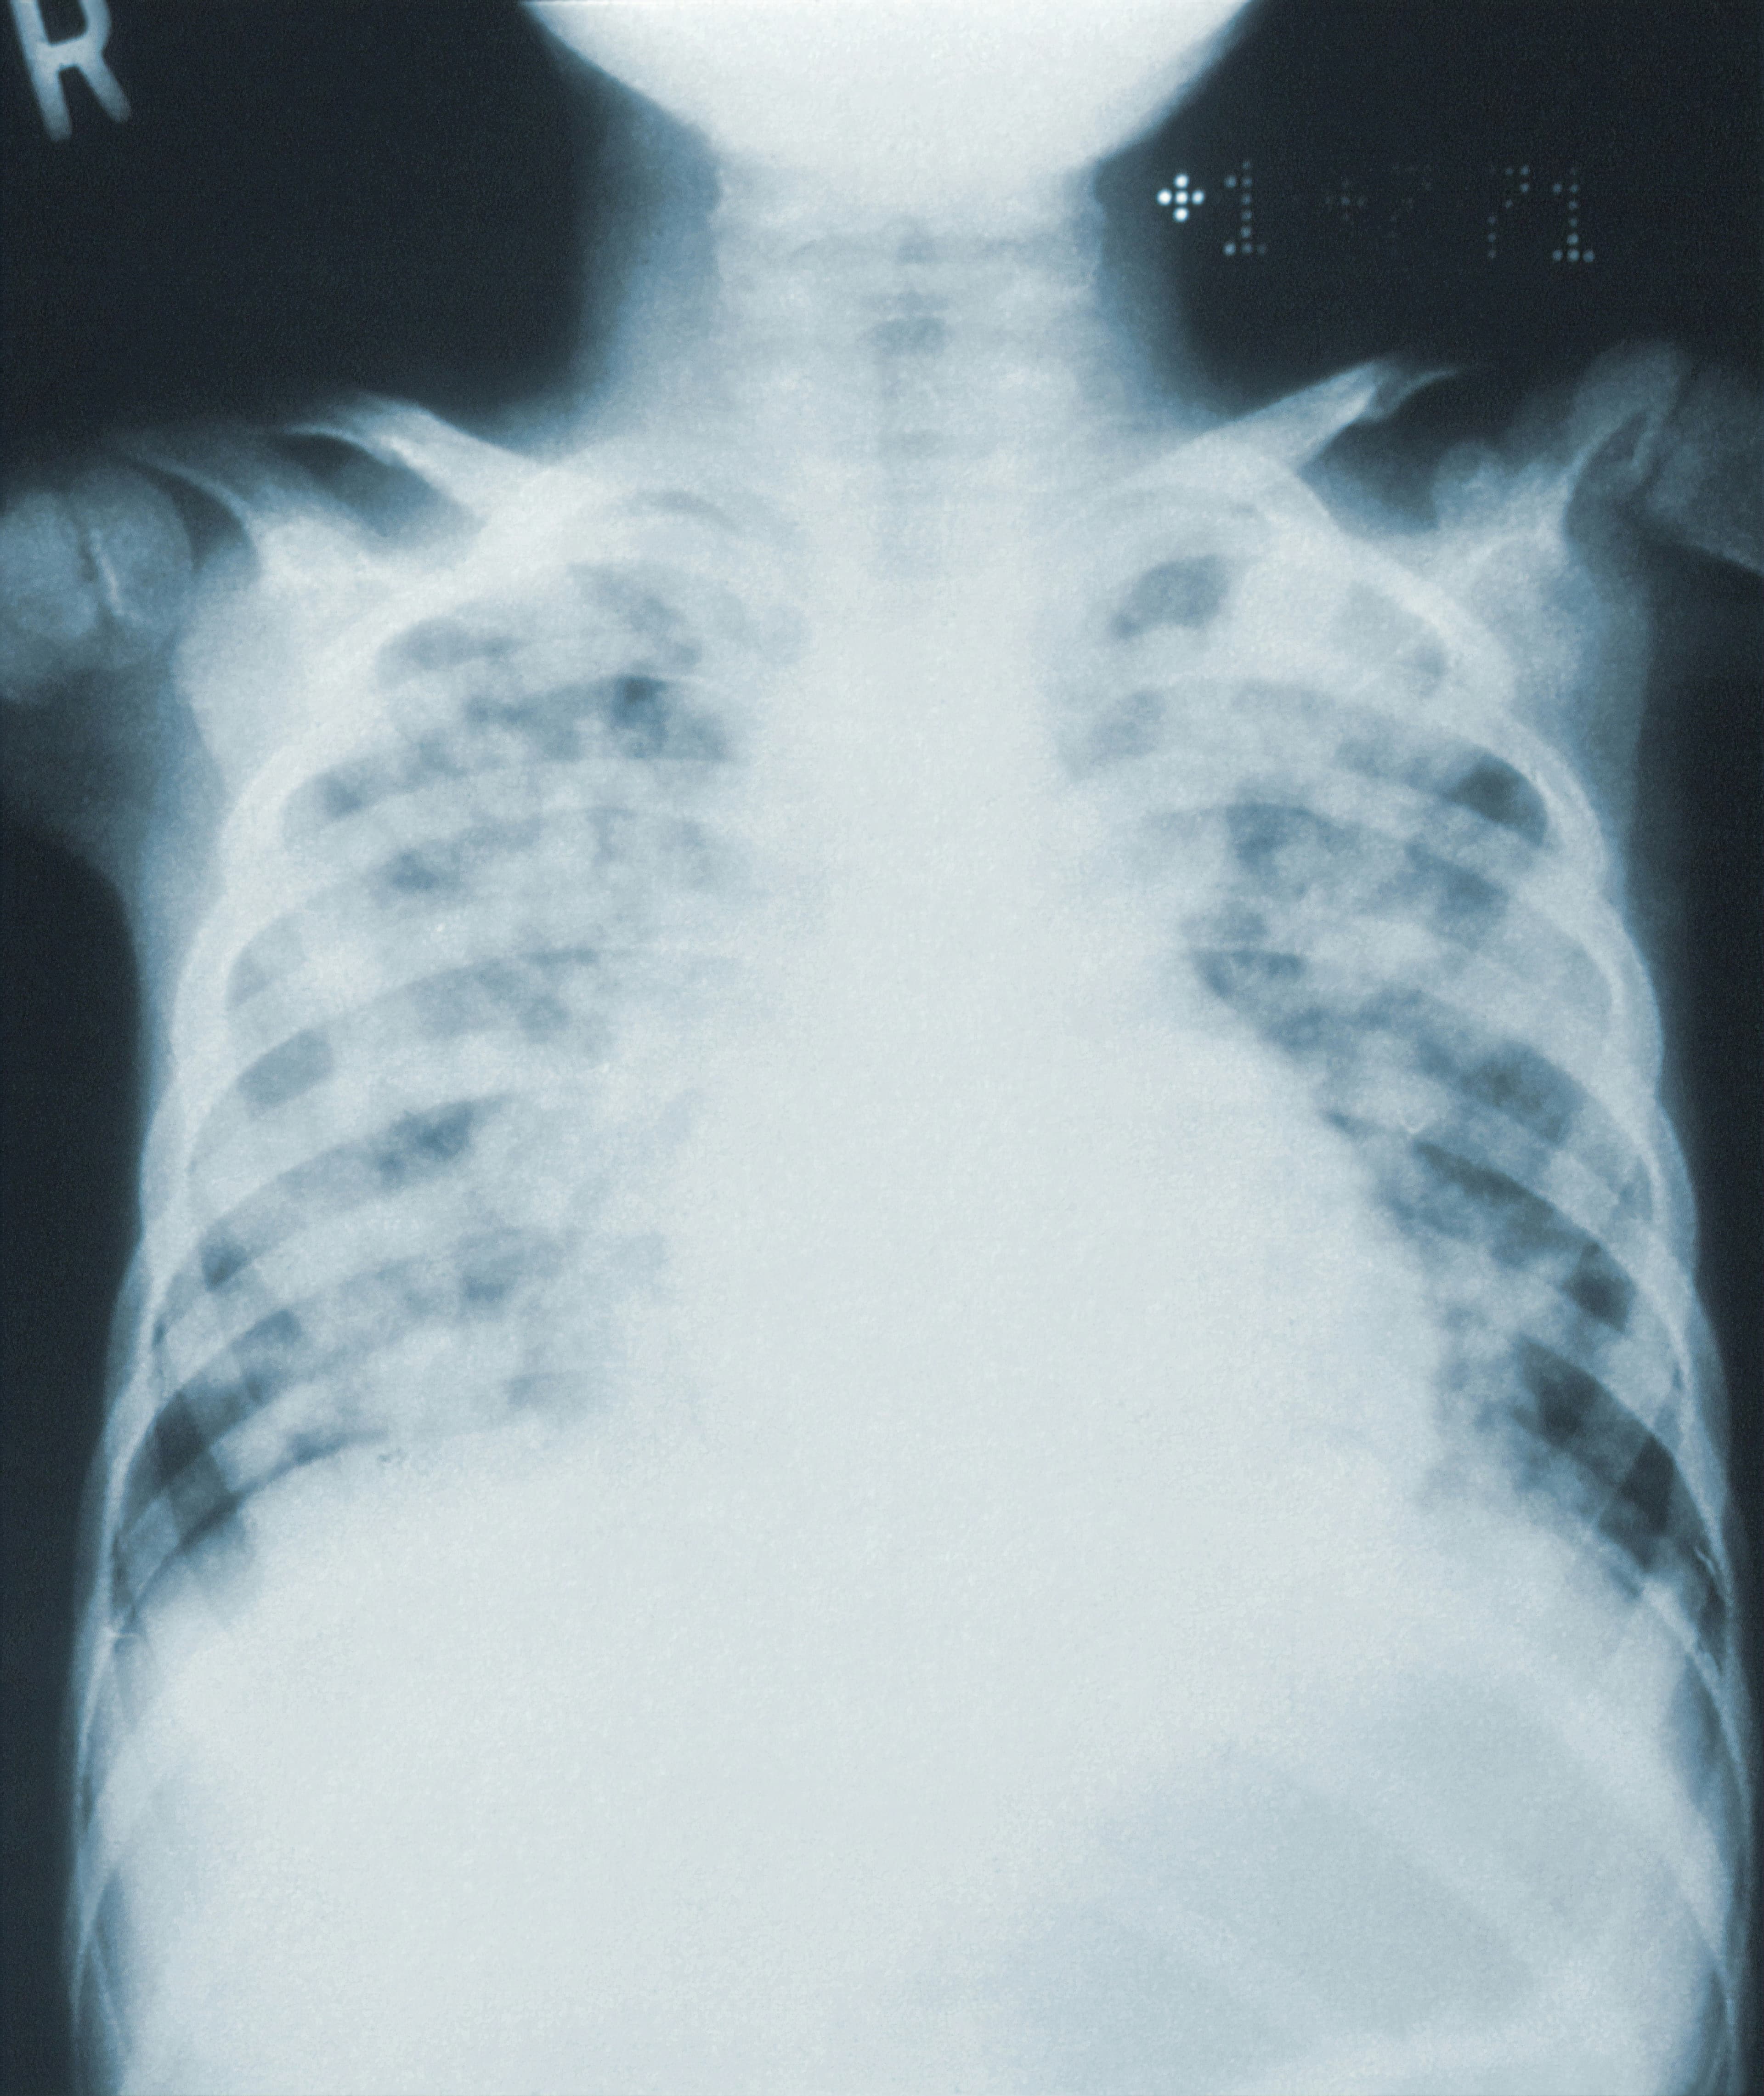

La lévothyroxine est une version synthétique de la thyroxine et est couramment prescrite pour traiter l'hypothyroïdie. Environ 23 millions d'Américains, soit environ 7 % de la population, prend de la lévothyroxine quotidiennement, parfois depuis de nombreuses années sans indication majeure. Or, il semble qu’une prise de lévothyroxine alors que la TSH se situe entre 0,4 et 5,0 mU/l soit associé à un risque accru de fracture osseuse.

Une prise de lévothyroxine prolongée pourrait entrainer une perte de densité osseuse